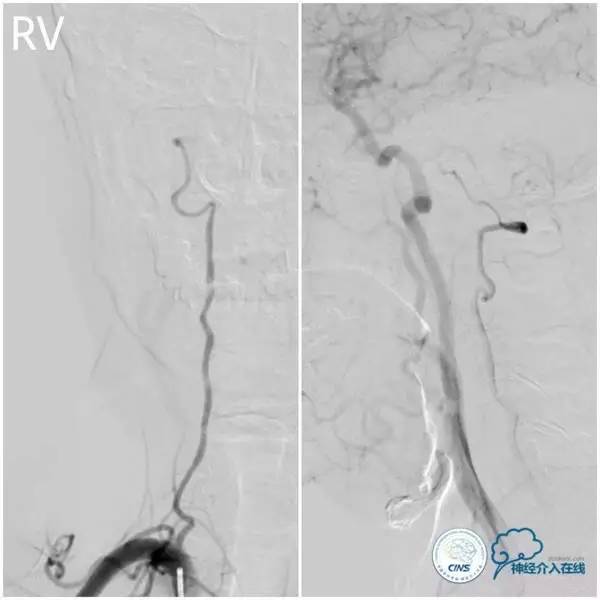

术前造影(图3-6):左椎动脉优势,左椎动脉V4段迂曲,基底动脉近段重度狭窄,双侧胚胎型大脑后动脉。

图3

图4

图5

图6